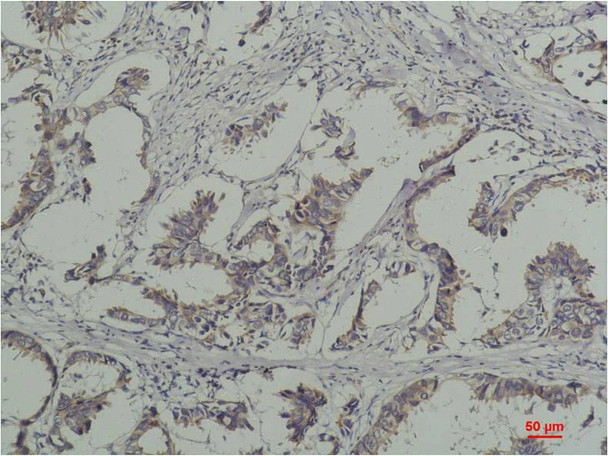

Immunohistochemical analysis of paraffin-embedded Human Breast Caricnoma using Phosphotyrosine Mouse mAb diluted at 1:200.